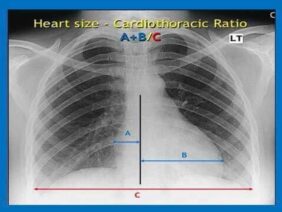

Para una radiografía del pecho, se suelen tomar dos vistas. Primero, usted se mantiene de pie con el pecho contra la película radiográfica y la imagen se toma desde la espalda. Los brazos estarán a ambos lados. Luego se suele tomar una vista lateral con los brazos por encima de la cabeza o en frente suyo. El técnico le indicará cuando debe respirar profundamente y mantenerse inmóvil. Para tomar una radiografía del pecho en personas que no pueden ponerse de pie, la película se coloca debajo de ellas y la imagen se toma desde el frente.